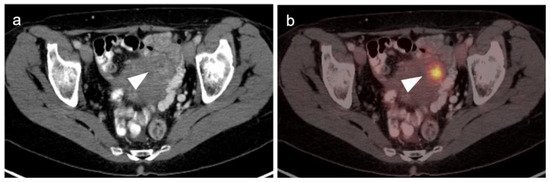

2.4. Cervical Cancer